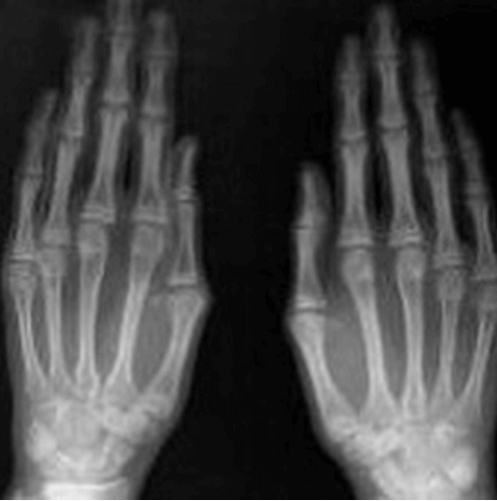

✅ 마르판증후군 (Marfan syndrome)은 결합 조직에 결함이 있는 유전 질환으로, 키가 크고 팔다리가 길며 허파, 눈, 심장, 혈관 등에 이상이 나타납니다.

ㅇ 이 질환은 15번 염색체에 위치한 피브릴린-1 단백질 유전자 (FBN1)의 중복이나 결함으로 인해 발생하며, 심혈관, 안구, 골격에 심각한 장애를 초래합니다

ㅇ 골격, 안구, 심장 혈관, 폐, 피부 및 외피, 경질막의 특징적 임상 증상과 가족력을 조사하여 진단합니다.